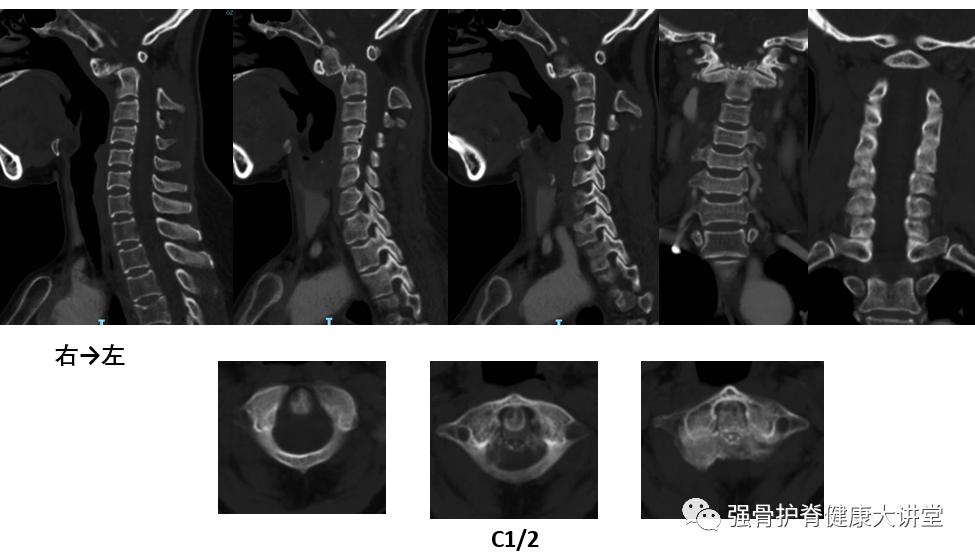

【术前资料】

颈椎中立位CT

颈椎过伸位CT

结合患者病史、症状体征及影像学检查,明确诊断为:1.寰枢椎脱位 2.颈部脊髓损伤 3.陈旧性颈椎骨折(齿状突) 经认真术前评估后,在梁德教授指导下,江晓兵教授带领团队为其施行前路显微镜下经口寰枢椎松解、枢椎齿状突骨赘磨除、后路C1滑脱复位、C1-C2后方植骨融合内固定术。